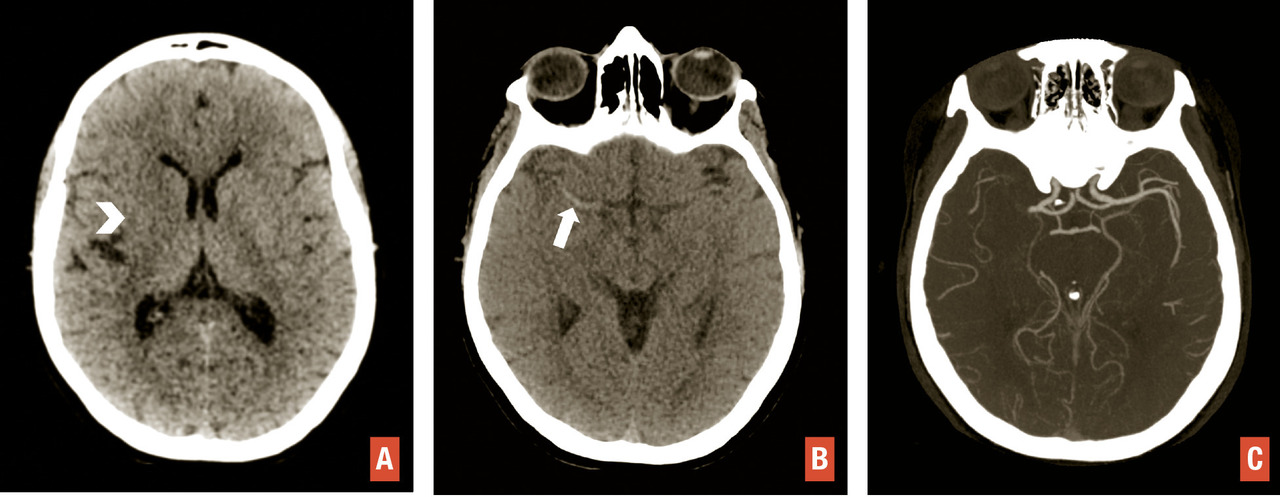

La tomodensitométrie (TDM) cérébrale garde une place centrale chez les patients suspects d’AVC, principalement en raison de sa large accessibilité, et en cas de contre-indication à l’imagerie par résonance magnétique (IRM). Sur le plan technique, elle est d’abord réalisée sans injection de produit de contraste, puis complétée par une angio-TDM des artères cervico-encéphaliques. La tomodensitométrie de perfusion peut venir compléter ces deux acquisitions, en cas de doute diagnostique ou pour guider la décision d’un traitement de recanalisation.2 En l’absence d’hématome, des signes d’infarctus peuvent exister sur une tomodensitométrie sans injection : dédifférenciation gris-blanc, effacement des sillons corticaux et hyperdensité spontanée de l’artère occluse (L’angio-TDM artérielle repose sur une acquisition lors du passage intra-artériel de produit de contraste iodé injecté par voie intraveineuse. Elle permet d’étudier les artères cervico-encéphaliques, à la recherche d’une sténose ou occlusion. L’angio-TDM dynamique (4D) renseigne également sur la qualité des collatérales suppléant le territoire ischémié.1

L’étude de la perfusion cérébrale repose sur des acquisitions séquentielles cérébrales itératives après injection d’un second bolus de produit de contraste iodé. Des logiciels dédiés permettent d’obtenir des cartographies de perfusion et d’estimer l’étendue respective de l’infarctus et de la zone de pénombre (hypoperfusée mais non encore infarcie). La présence d’une occlusion proximale permet d’orienter le patient vers un site de thrombectomie dans les 6 premières heures. Au-delà des premières heures, les images de perfusion sont essentielles pour guider la décision d’un traitement de recanalisation (thrombolyse intraveineuse après 4,5 heures, thrombectomie après 6 heures).1